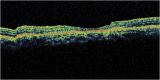

Results: A 6-year-old girl with thalassemia major who was on chronic multiple blood transfusions since 2 years of age presented with blurred vision in both eyes for 2 months. Blood reports showed very high serum ferritin levels in the range 400 to 2,250 ng/mL (checked every 3 months) since 4 years of age. She was on oral iron chelator deferasirox for 2 years, which was stopped a month ago. Fundus examination of both eyes showed a characteristic bull's eye macula with a purplish hue in the outer ring probably due to iron deposition. The center of the bull's eye had a beaten bronze appearance.